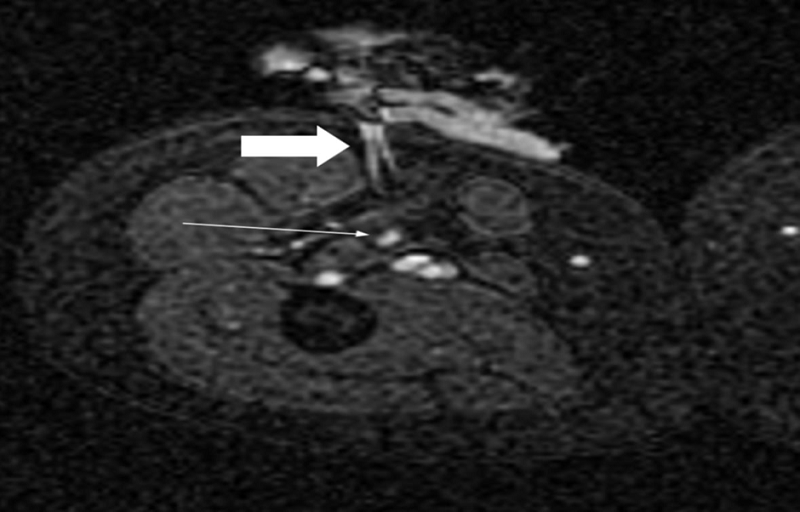

圖:一位78歲肝細胞癌患者結合TACE和RFA療法

CBCT是一種多功能工具,可以獨立地執(zhí)行這兩個療法。一些關于肝細胞癌和MWA或RFA與TACE聯合治療的研究表明,它可以改善臨床結果:特別是,與單獨 TACE 相比,它表現出更長的無進展生存期和相當的并發(fā)癥發(fā)生率。在用MWA和腎動脈栓塞治療的一系列T1a腎細胞癌病例中也記錄了有希望的結果。然而,還需要進一步的研究。